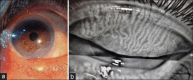

Demodexblepharitis (DB) has become one of the common differential diagnoses in patients presenting with red eyes in daily clinics. In this review article, we have incorporated a detailed discussion about the mite and the various mechanisms by which it causes different signs and symptoms, the risk factors, and diagnostic methods with current and emerging treatment modalities. Because of the chronic symptoms and rather a late diagnosis, DB considerably affects patients' quality of life. The clues to identify cylindrical dandruff, the diagnostic sign of Demodex, visualization of the mite correlating their presence with signs and symptoms, and instituting early and appropriate treatment are the goals of this article.